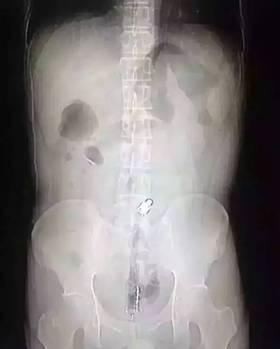

“因為物體邊緣比較光滑,手術(shù)的時候,我們兩個人合作,一個人順著肚子一點點推,推到肛門口,我把異物拿了出來,大概花了十分鐘時間。”郁峰說,這名男子運氣算好的,因為根據(jù)拍片檢查,當(dāng)時那根振動棒已經(jīng)擠到了肚臍的部位,情況其實已經(jīng)相當(dāng)危險。醫(yī)生提醒 “那根振動棒有20公分,人的直腸只有18公分,它的長度已經(jīng)超過直腸了,到達(dá)乙狀結(jié)腸,會引起腸子破裂壞死,如果破了就會有生命危險 。 ”